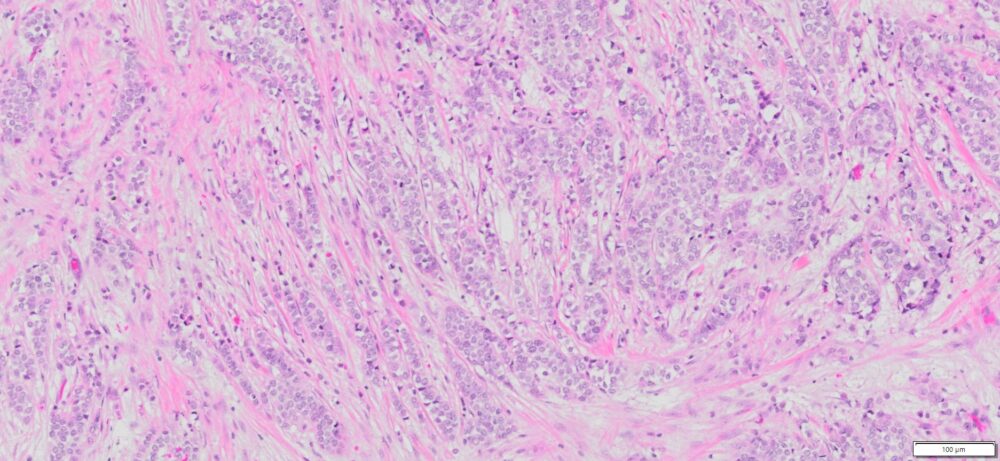

Description

| SKU# | Organ | Pathology Diagnosis | Therapies (Chemotherapies ,radiation and Hormone) before Collection of Sample |

Gender/Age (year) | Tumor Area(%) | Tumor Grade | TMN/Stage | ER,PR & HER2 IHC Data |

| HuPS-02032T1 | Breast | Invasive lobular carcinoma | No | Female/47 | 45 | II | pT1c pN0Mx | ER(+)/PR(+)/Her2 (+),E-Cadherin (-) |

Slide Preparation

Human tissue was fixed in formalin immediately after excision and embedded in paraffin. The tissue sections were 5 µm in thickness and mounted each on positively charged glass slides.